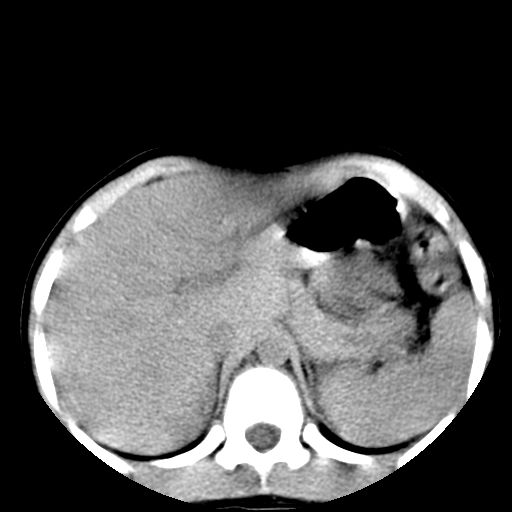

腹部好象未见异常。

腹部ct平扫未见明确异常

腹部ct平扫不能提示哪里有病变。